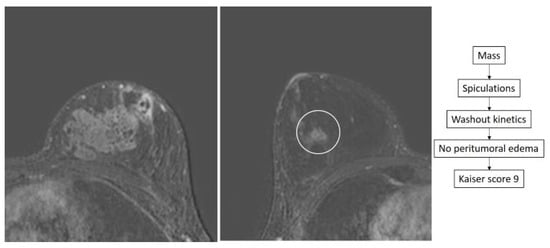

- Dietzel, M.; Baltzer, P.A.T. How to Use the Kaiser Score as a Clinical Decision Rule for Diagnosis in Multiparametric Breast MRI: A Pictorial Essay. Insights Imaging 2018, 9, 325–335. [Google Scholar] [CrossRef] [PubMed]